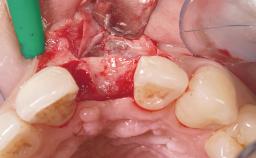

A 36-year-old female patient was referred for the replacement of the upper left central incisor (tooth 21), which had fractured. Although the tooth had been asymptomatic for many years, the crown began to loosen, at which time she presented to her dentist for an assessment. Teeth 21 and 22 had both been endodontically treated many years previously. She was a healthy individual and a non-smoker.

| Bone Augmentation | Horizontal|Staged |

| Augmentation Materials | Xenogenous|Membrane |

| Soft Tissue Grafting | Simultaneous |